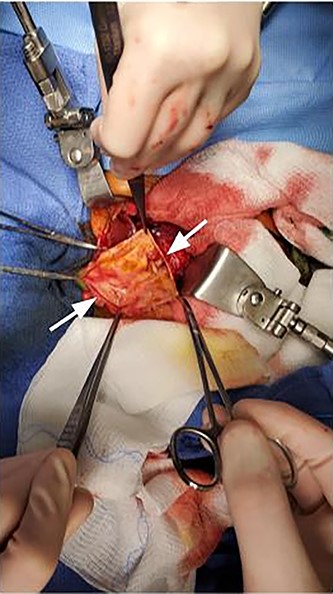

Intraoperatively, a large cystic structure, noted to be the CC, was identified spanning the right upper and lower quadrants down to the pelvis, displacing surrounding tissue. Following the cholecystectomy, the CC was freed circumferentially, identifying and preserving the right hepatic artery. Once the cyst was able to be elevated off of the portal structures, the decision was made to drain the cyst. The cyst was entered at the level of the common hepatic duct below the bifurcation, and significant bilious sludge was aspirated. Once the cyst was drained, it was excised from just proximal to the bifurcation of the left and right hepatic ducts to the distal CBD which was oversewn after clear identification of the pancreatic duct (Fig. 2). Reconstruction was performed with a Roux-en-Y hepaticojejunostomy with a retrocolic 45 cm Roux limb. A 10-French drain was left in the right upper quadrant and the abdomen was closed. The final excised specimen is shown in Fig. 3. Microscopically the cyst surface was entirely denuded with absent mucosa, the wall was composed of quiescent, uniform fibrocytes. The superficial zone of the cyst wall was congested and hemorrhagic Fig. 4A-4B. The CBD was mildly dilated with intact mucosa (Fig. 4C-4D). There were no apparent complications and the patient tolerated the procedure well. The postoperative course was notable for asymptomatic bradycardia that self-resolved. Feeds were initiated on the fourth postoperative day, surgical drain was removed on the sixth postoperative day, and the patient was ultimately discharged home on the seventh postoperative day. Follow-up ultrasound within 1 week of discharge showed typical postoperative changes without evidence of fluid collection or biliary ductal dilation, and normal appearance of the liver without evidence of fibrosis. LFTs also normalized (TB 0.7 mg/dl and DB 0.2 mg/dl). The patient was most recently evaluated in clinic at 8 weeks of age at which time she was feeding and stooling appropriately.